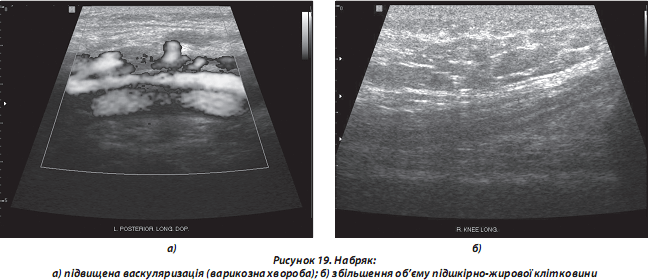

4. Патологія підшкірно-жирової клітковини:

а) набряк спостерігається при запальному процесі (артрити, періартрит тощо), хронічній серцевій та венозній недостатності, лімфедемі, целюліті тощо). При УЗ-дослідженні визначають збільшення об’єму ПЖК, зміни ехогенності (найчастіше суттєва гіпоехогенність сполучнотканинних фіброзних перегородок на фоні відносно гіперехогенних прошарків жирової тканини) (рис. 19);